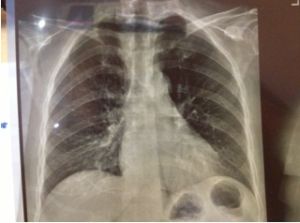

2.X線檢查

早期雖有呼吸困難,但X線胸片可能基本正常;中後期出現兩肺中下野彌散性網狀或結節狀陰影,偶見胸膜腔積液,增厚或鈣化。